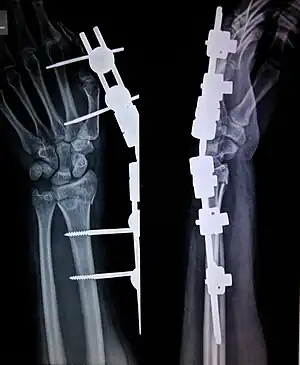

External fixation is a surgical treatment wherein Kirschner pins and wires are inserted and affixed into bone and then exit the body to be attached to an external apparatus composed of rings and threaded rods — the Ilizarov apparatus, the Taylor Spatial Frame, and the Octopod External Fixator — which immobilises the damaged limb to facilitate healing.[1] As an alternative to internal fixation, wherein bone-stabilising mechanical components are surgically emplaced in the body of the patient, external fixation is used to stabilize bone tissues and soft tissues at a distance from the site of the injury.

In the 1950s, in the USSR, Dr. Gavriil Ilizarov devised and developed and applied the Ilizarov apparatus for treating and resolving fractures, deformities, and defects of the bones of the limbs. A metal frame encircles the limb is attached to the underlying bone by crossing (X) pins inserted through the bone and limb. The external rings are linked to each other by threaded rods and hinges that allow to move the position of the bone fragments without opening the fracture site, then the fragments can be fixed in rigid position until complete healing.

In this kind of reduction, holes are drilled into uninjured areas of bones around the fracture and special bolts or wires are screwed into the holes. Outside the body, a rod or a curved piece of metal with special ball-and-socket joints joins the bolts to make a rigid support. The fracture can be set in the proper anatomical configuration by adjusting the ball-and-socket joints. Since the bolts pierce the skin, proper cleaning to prevent infection at the site of surgery must be performed.